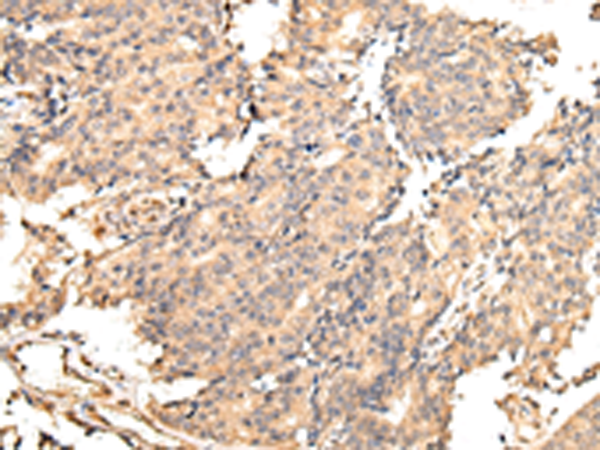

分类: 科研抗体货号: P08918别名: Ptg-2; TSC22; TGFB1I4应用: IHC反应种属: Human, Rat